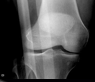

Knee pain following a soccer injury

William Yaakob, MD; Stephen Schabel, MD

<p>A 23-year-old woman presents with severe right knee pain that resulted from a collision with another player during a soccer game. The majority of the force of the blow was to the right knee. The...